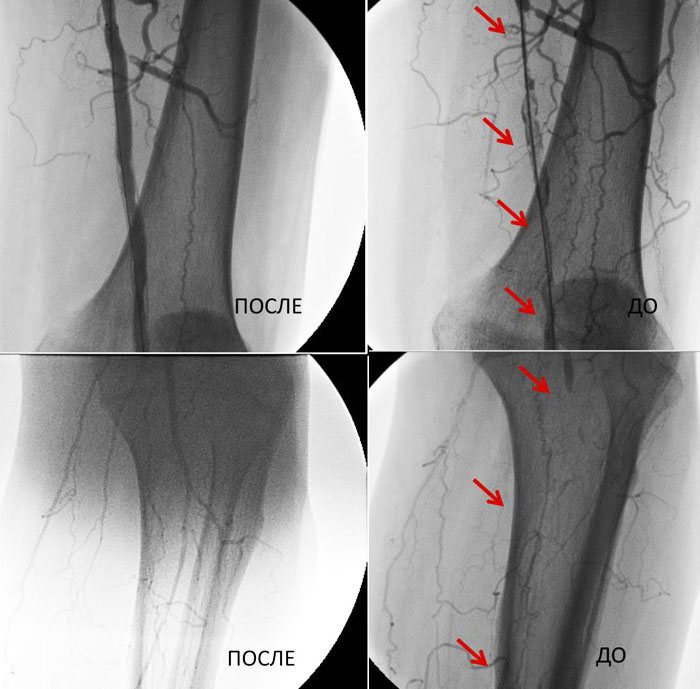

Фотографии До и После

Результаты артериральных реконструкций

До и После